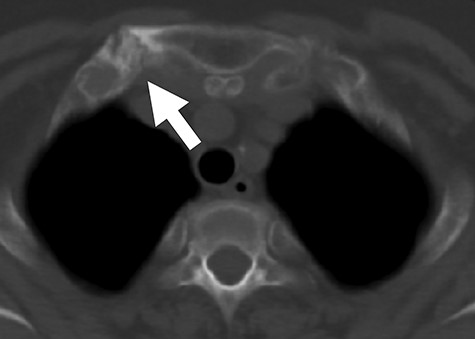

Axial CT image demonstrating thickened right sternoclavicular joint (white arrow). CT, computed tomography.